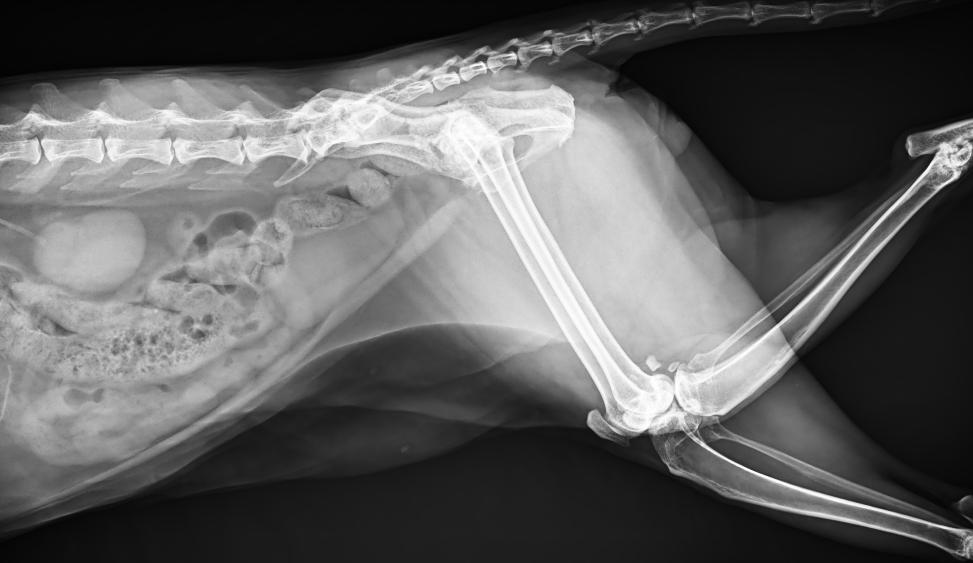

● 進(jìn)口高品質(zhì)球管,大功率、高熱容量、微焦點(diǎn),1.0/2.0mm雙焦點(diǎn)設(shè)計(jì)

● 25kHz高主逆變頻率,輸出電壓更穩(wěn)定;瞬時(shí)定格影像,無(wú)拖尾現(xiàn)象

● 可浮動(dòng)床面設(shè)計(jì),滿足大部分中小型寵物檢查